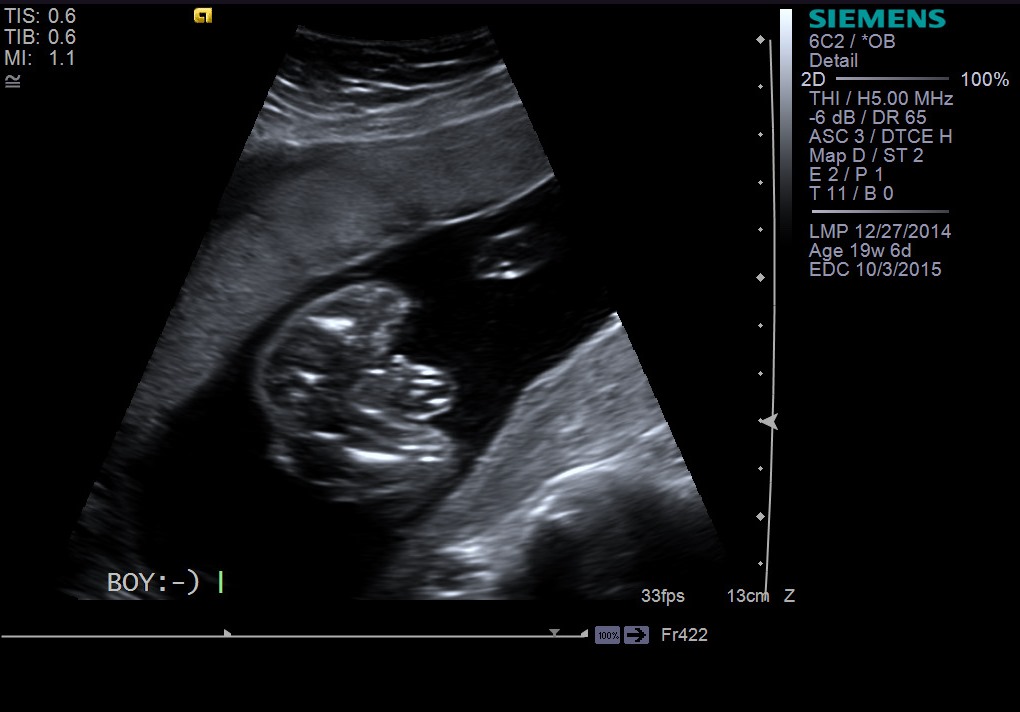

20 week ultrasound picture looks different than others (potty shot)!

I posted this on IG as well but looking to get additional thoughts on my 20 week anatomy scan picture that shows gender. At our 20 week scan on Friday, they confirmed we are having a boy! I'm really not doubting it but I just can't get past how my picture looks much different than most people's 20 week boy potty shots. Any additional thoughts or feedback would be great on what you see when you look at this picture, any thoughts on what that big bulge is? Tech pointed out scrotum and boy parts but I don't really see clearly what she is seeing (which isn't a surprise because I am no expert). Thanks for your thoughts!! :)Attachment 25307